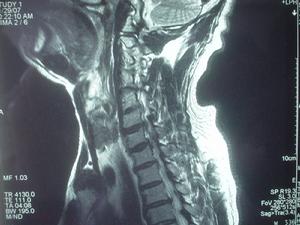

胸椎間盤膨出-影像學檢查

(2)脊髓造影:用大劑量的水溶性造影劑行脊髓造影術的同時用CT掃描,是一種更準確的優良診斷方法。如不先行脊髓造影,而直接用CT檢查,將會弄錯受損脊髓的準確節段。但目前大多數學者均認為此種損傷性檢查應被MRI檢查取代,因為後者也是一種縱向觀察估測整個胸椎椎管的方法。

(3)CT及MRI檢查:凡疑及本病者,均應及早行MRI檢查。作者發現,MRI檢查是本病早期診斷及獲取及時治療最為有效的措施。此外,脊髓造影及CT檢查等雖對本病的診斷亦有一定幫助,但由於其確診率不如MRI檢查,因此,切勿作為首選檢查項目,目前已較少選用或僅作為參考。